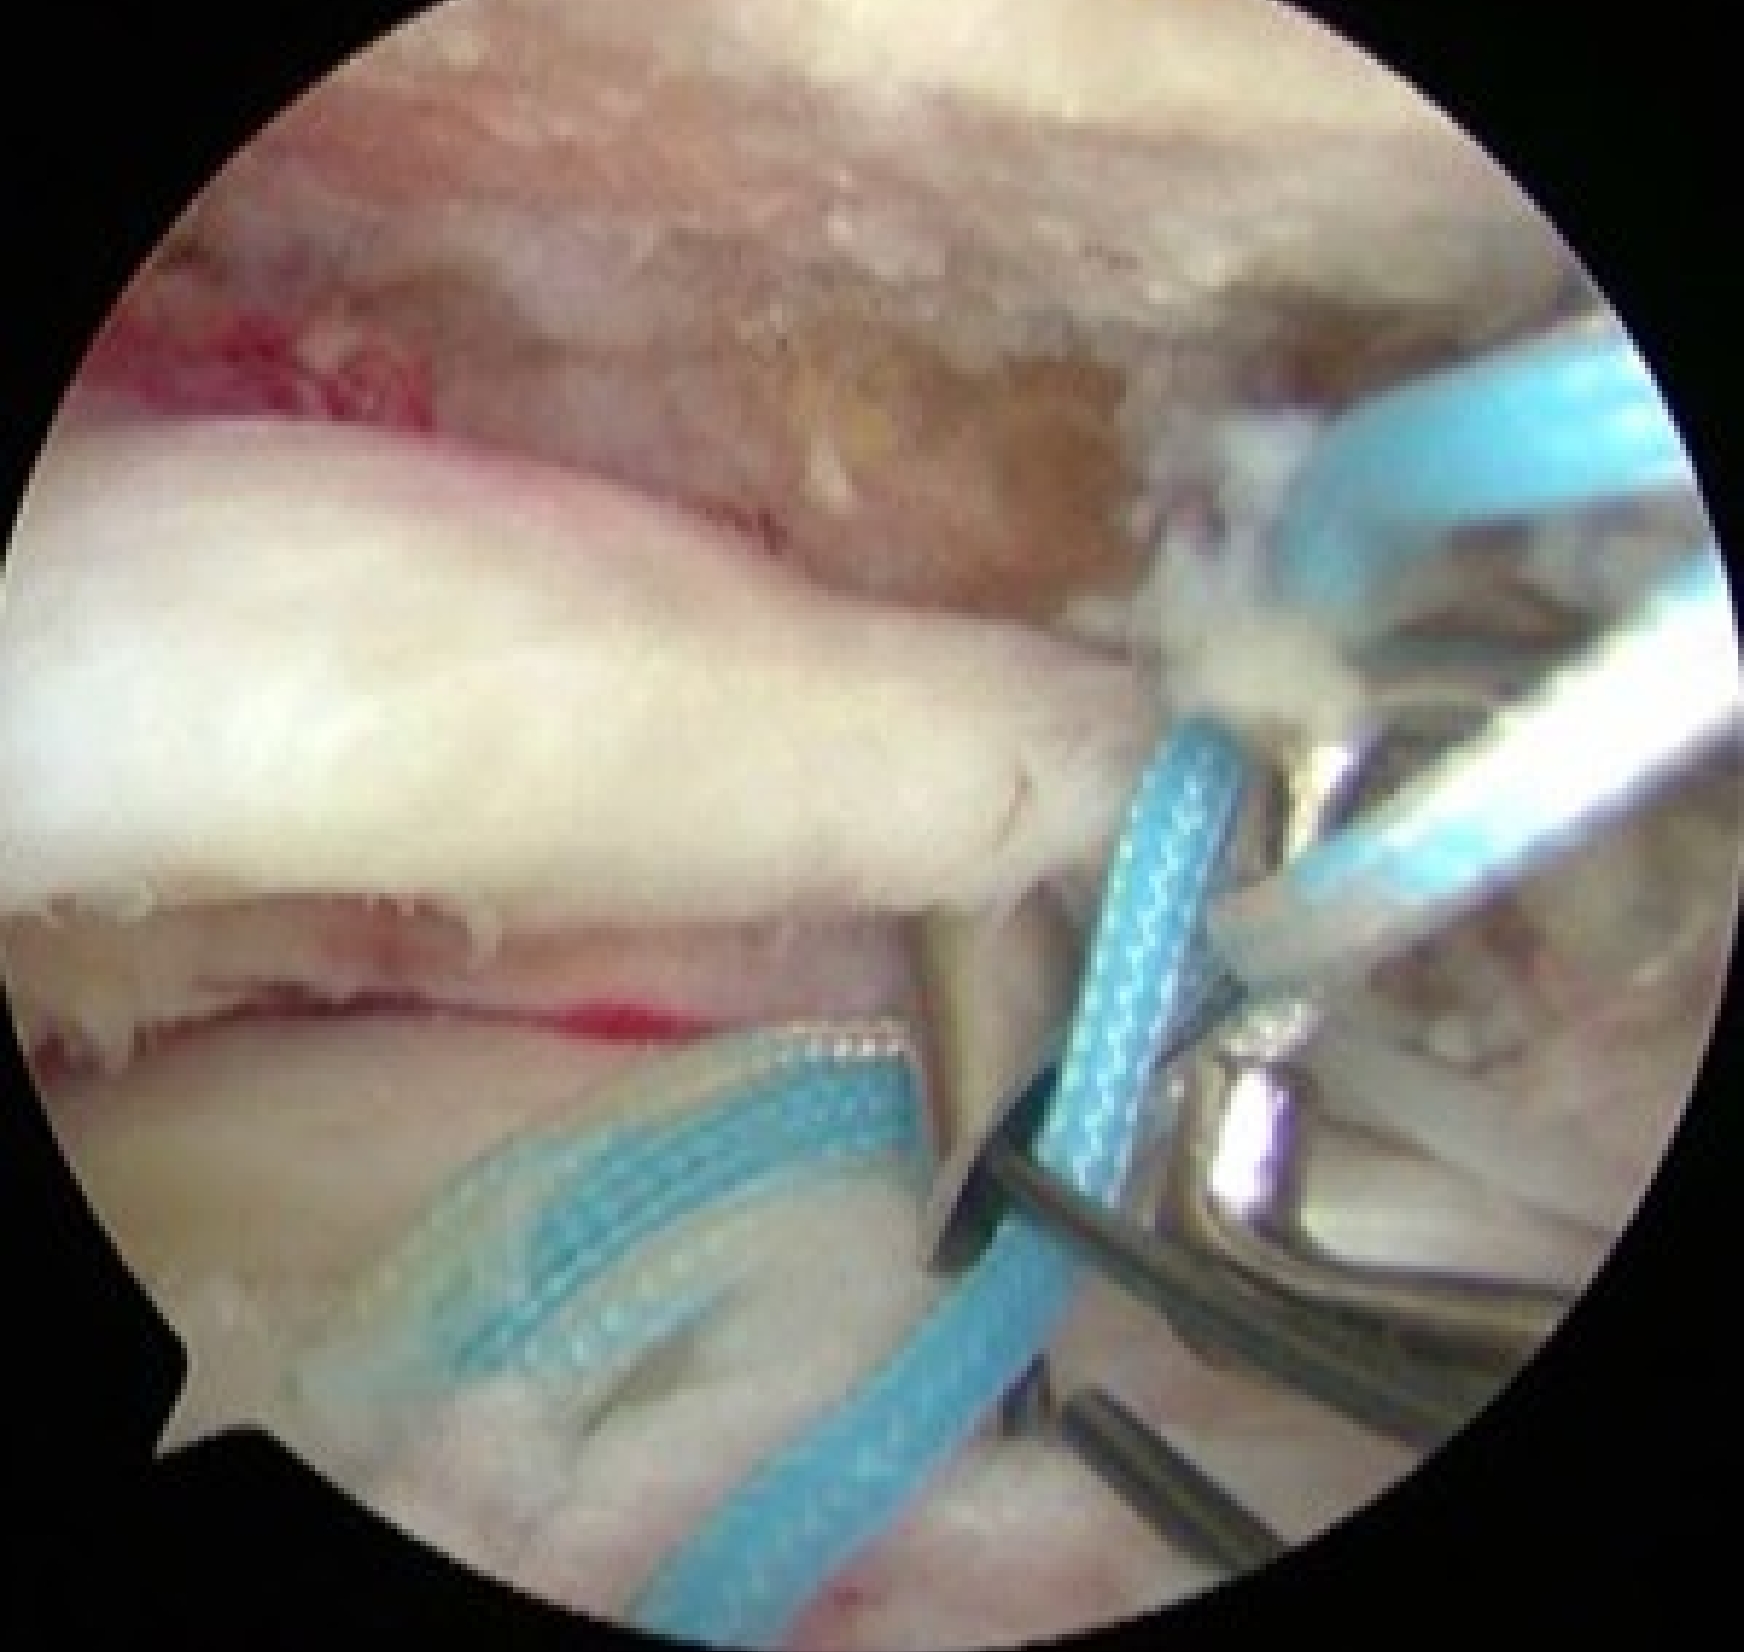

⑤上腕二頭筋長頭筋腱(LHB)の腱固定

外側アンカー設置

Suture-bridge完成

露出していた骨頭は見えなくなり、腱板で覆われています。